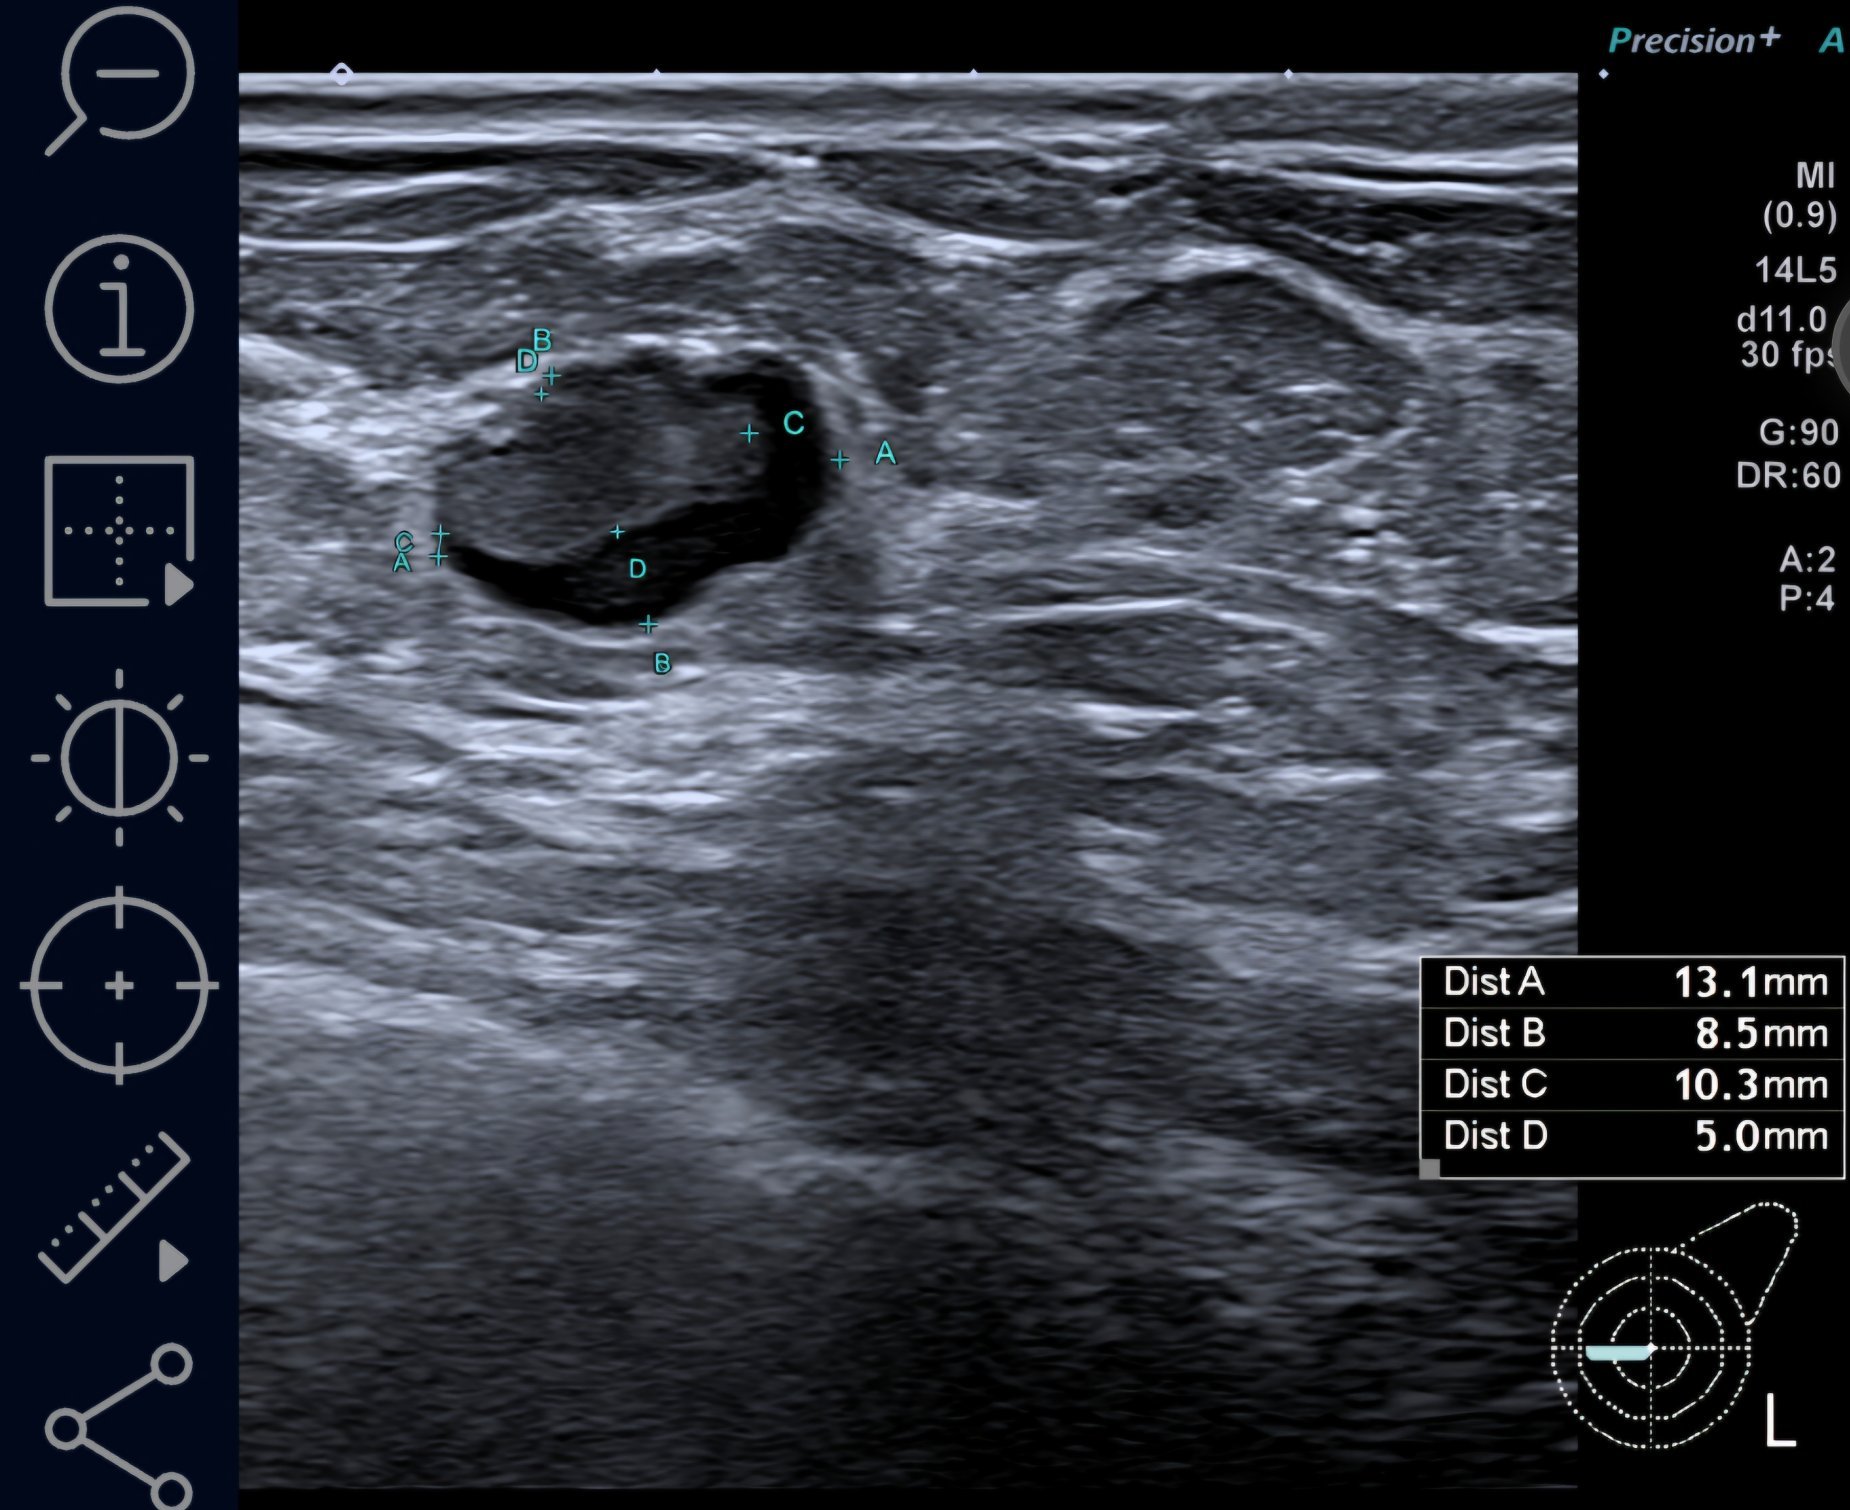

Далинда, ето малко картинки от BIRADS 4c ( най- вече вляво) , само по образни. Това са първите картинки, оттогава имам още нови попълнения. Биопсията не показа точно какво е и какво не е, според лекарите може би не са "уцелили" точното място в лезията, защото има известно разминаване. Вчера бях на ПЕТ, само сумтяха и ми казаха, че ще разбера резултатите от лекуващата другата седмица, след като е минала Туморната комисия 🤷‍♀️

Marie curie, твоето само по формата и е силно подозрително за рак. Неправилни, наръбени форми са червена лампа.